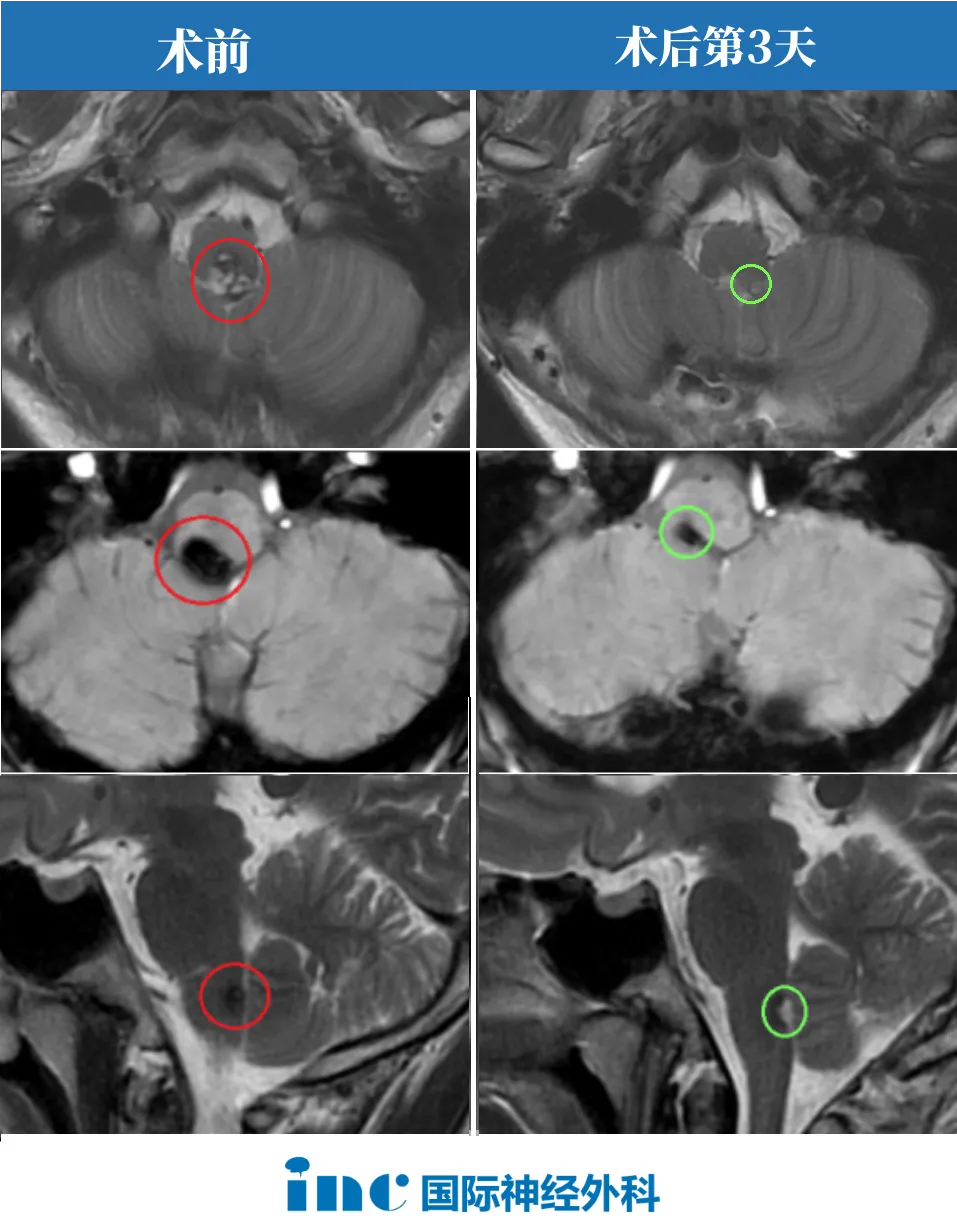

04、2023年3月29日:“全切全切”——顺利手术了

“全切全切了!”在国内手术团队的配合下,术中神经电生理监测下,巴教授全程主刀顺利全切了安豪的脑干海绵状血管瘤。